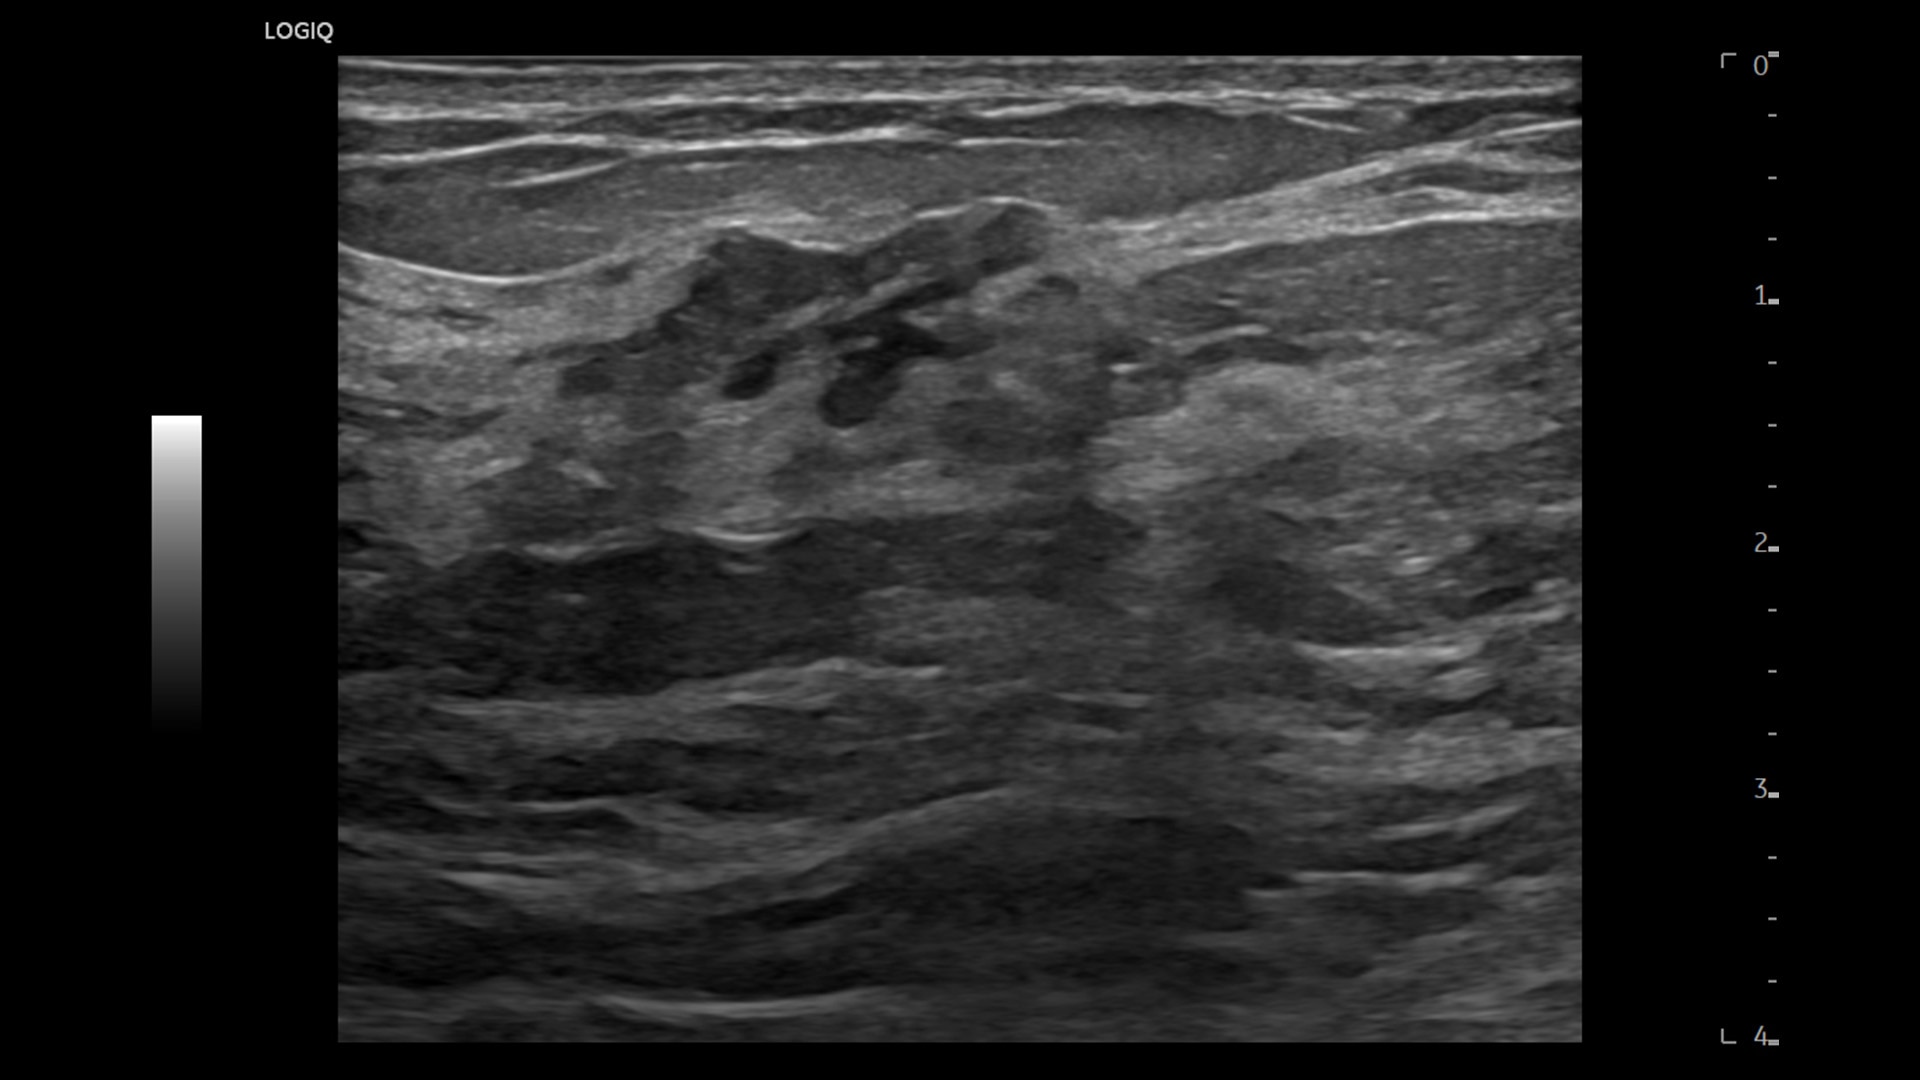

Strength and power to enhance clinical capabilities and deliver exceptional image quality